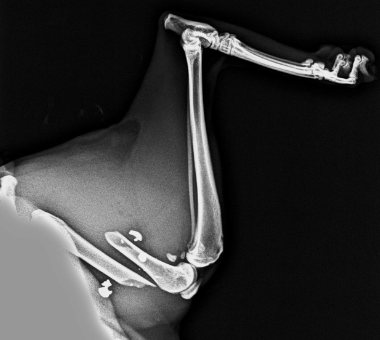

danisubi Publicado 29 de Julio del 2017 Reportar Publicado 29 de Julio del 2017 Hola a todos. Ya se que el foro va de radares, pero quiero dejar constancia de lo que paso ayer. Tenemos 4 gatos y dos perros. Todos ellos vacunados (los perros incluso con vacuna de la leishmania), con chip y esterilizados menos nuestra perrita pequeña que tiene 9 meses y justo acaba de pasar el primer celo. En agosto la esterilizamos tambien. Ayer a las 8:30 am, estando nuestro gato pequeño de dos años encima del muro de nuestro jardin, recibio un disparo que le ha partido el femur y le ha dejado plomo incrustado en la masa muscular. La escopeta usada es una antigua del calibre 5 o 5 y medio y con salida de un solo perdigon. No ha sido un niño descerebrado que se dedica a disparar a los animales en verano. Segun el veterinario de trauma que lo operara, ha sido sabiendo lo que hacia y apuntando bien a unos 40-50 metros. Como tengo armas y bastante punteria, se que el cabron tiene que haber estado al menos unos 12 segundos apuntando a la pata, a sabiendas que le partiria el femur. Hasta la semana que viene no tenemos hora para la operacion. Le pondran clavos y cuando se suelde, operaran otra vez para quitarselos. El problema esta en que de momento no saben que afectacion puede tener la incrustacion del plomo en los musculos. Hay mucho hijo de puta suelto. Todos los vecinos sospechamos quien ha sido, pero se ha derivado la investigacion a la guardia civil. Uno por disparar en nucleo urbano (esta prohibido) y otra por disparar a un animal (maltrato animal, que por suerte tiene pena de carcel). Estaba encima de nuestro muro y cayo de golpe. Nuestros dos perros salieron al jardin cagando leches y ladrando para socorrerle pero el gatito solo bufaba y ya no podia andar. Se arrastraba con las patas delanteras. Os pongo la foto de la radiografia donde se ve el femur partido y los restos de plomo incrustados en los musculos. Citar

danisubi Publicado 31 de Julio del 2017 Autor Reportar Publicado 31 de Julio del 2017 Ya estamos con nuestro gatito en casa. Lo han operado en 1 hora y 46 minutos. Le han podido quitar un poco de plomo, pero por que lo habia pedido yo para llevarselo a la gc. No se ha atrevido a mas por miedo, ya que segun me ha dicho esta muy incrustado, y para quitarlo tenia que manipular entre el nervio ciatico y la vena femoral. Asi que no se lo ha podido sacar. Vamos se ha quedado casi todo dentro. De todas formas, nos han dicho que no le deberia afectar y que, a veces, lo suelen ir expulsando con el paso del tiempo. Y ahora, la realidad. De momento no se sabe como quedara. Primero debe hacer caso y no saltar (ya dificil en un perro, pues en un gato imposible). Hemos trasladado todos los muebles de la habitacion donde estara solo y tranquilo a la buhardilla y solo le hemos dejado un tatami. Asi no se liara a saltar. Pero claro, es un gato, no un perro obediente. La semana que viene a revision de la intervencion pero debera llevar los clavos durante 40 dias. Si se le ocurre hacer el loco, los clavos podrian partir el hueso y quedarse cojo para siempre. Una de las imagenes que pondre ahora, pueden herir sensibilidades. No hay sangre, tan solo la brecha de la operacion. Y la pongo para que veais la magnitud que tiene esto y compareis eso en una pierna humana. Os pongo foto de nuestro gatito en el transportin, recien sacado de la jaula de reposo y la radiografia antes de cortar los clavos. Podeis observar como han unido el femur. . Citar